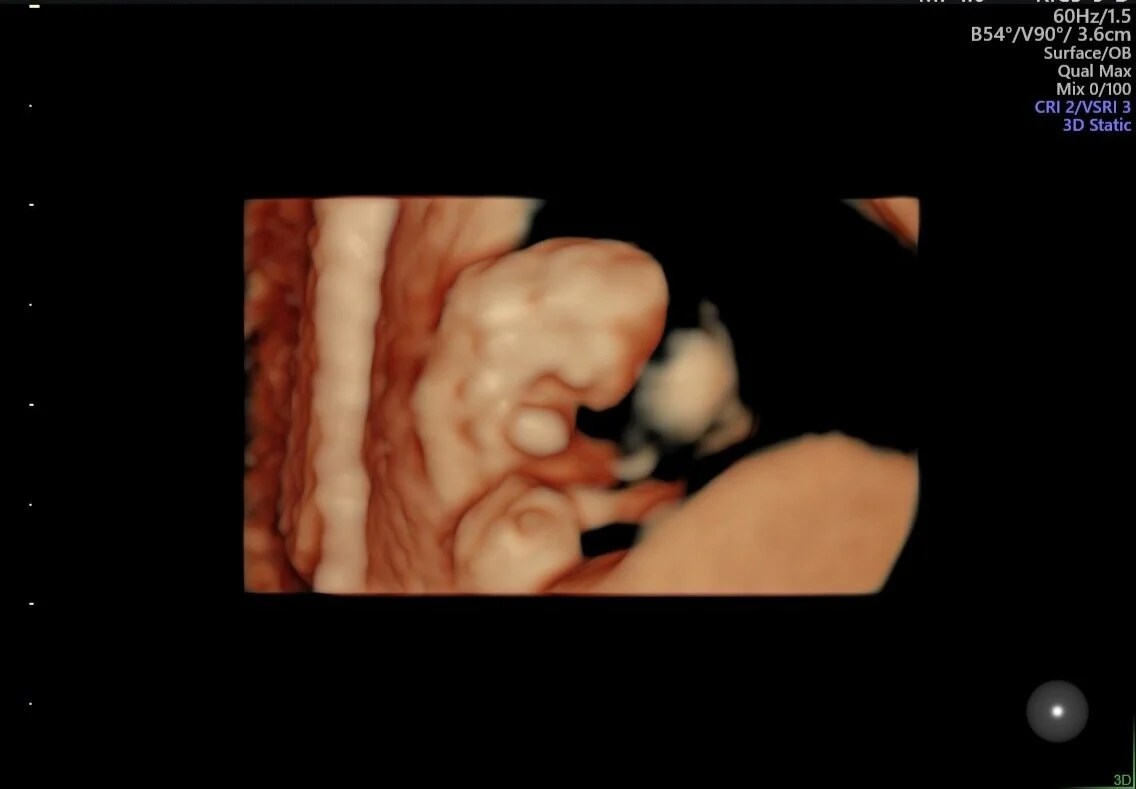

Fmfla Medicina Fetal Ultrassonografia 1º Trimestre

Desenvolvimento Do Bebe 11 Semanas De Gestacao Tua Saude

9 Semanas De Gestacao Trocando Fraldas